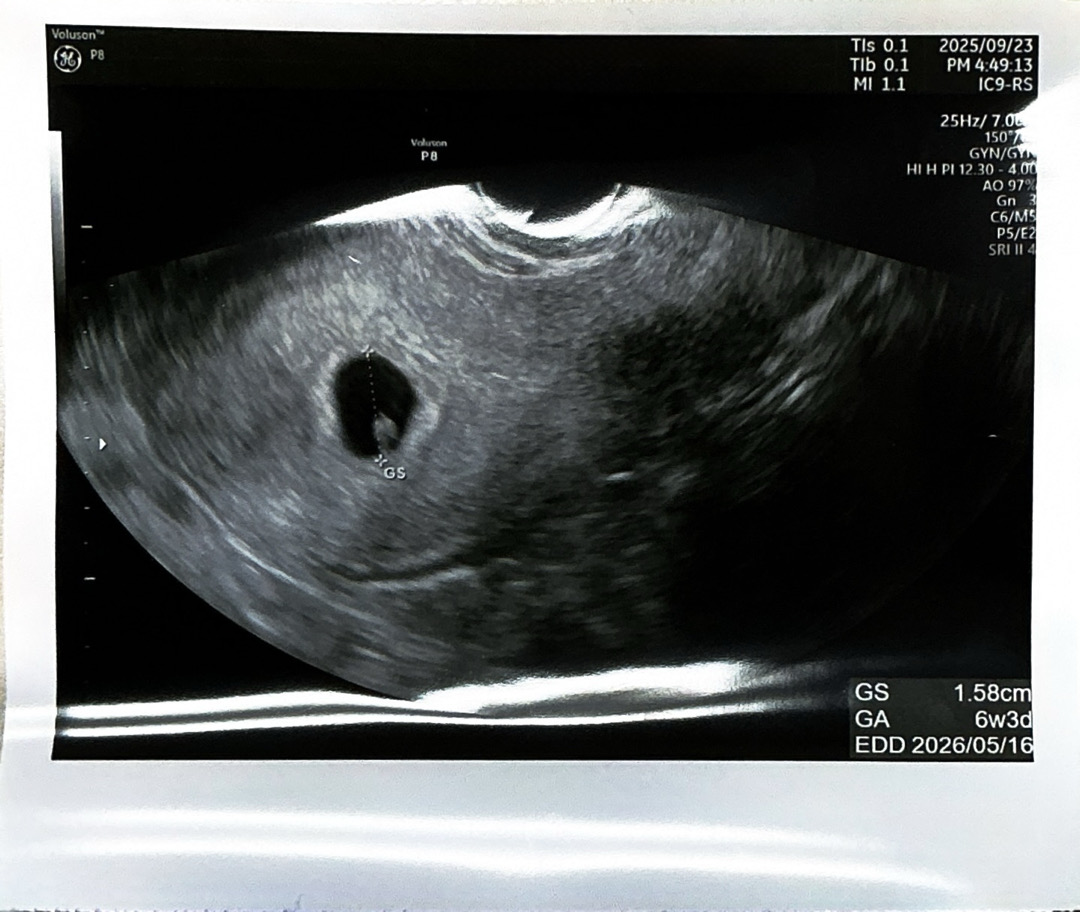

지난주에 몸이 너무 피곤하고 생리도 계속 안해서 혹시나하고 월요일에 임테기 하고 병원 갔더니 벌써 6주 3일이래요 🫢 놀이공원도 몇번이나 다녀오고 군것질, 커피 엄청 먹었는게 주마등처럼 지나가네요😥 다들 근데 6주차면 심장소리 듣고 다이아몬드 본다는 글이 보이는데.. 저는 2주뒤에 오라네요 ㅠㅠ 제 초음파 좀 봐주세요~ 괜찮은건가요? 다이아몬드는 언제쯤 볼 수 있는걸까요?ㅎㅎ 추석 전에 심장소리 들을줄 알고 추석때 양가부모님께 말씀드리려했는데 그냥 먼저 말씀 드려야할거같아요